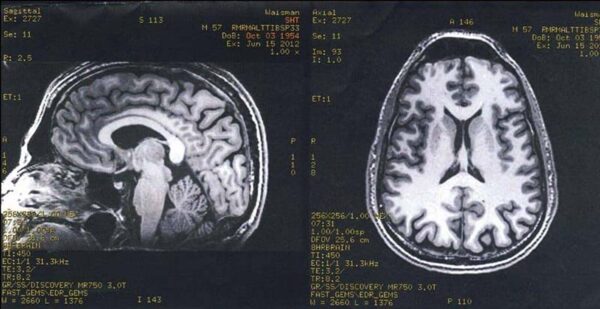

e finished that up and I got up to get ready for the lab. The technician at the computer screen behind me in the picture said, “Steve, what’s your middle initial?” I said, “H. Stephen Horton Tibbetts.” He hesitated a moment, tapped something into his keyboard, hit return, and I saw the letters “SHT SCAN” on the top of his monitor. (Later on, at dinner, Mom laughed and said, “Oh. Sorry. Sorry about that. I never thought about that when we named you.”)

I popped in some ear plugs they gave me (the machine was loud) and put the respiration belt around my middle. I laid down on the sliding panel, the technicians attached the heart monitor and other devices to my hands, and they slid me into the machine. It started whirring and clunking. The technicians closed the door to the lab and went back into the control room. My heart was beating really fast, and knowing that Antoine and the technicians were monitoring my heartbeat made it speed up even more. We started. Open Presence. Burning. Focused Attention. Burning. “Put your hand in the box.” There were speakers inside the machine. Antoine occasionally asked, “How are you doing?” I always replied that I was doing fine. The machine was very loud, and I couldn’t really move my neck or head for quite some time. Amazingly, the burning pad did not leave a mark on my skin.

But he didn’t. The technician took our picture, and then Antoine and I spent some time in the control room talking. Richie came in, hugged me, and gave me an autographed copy of his book.

Into the machine

Done